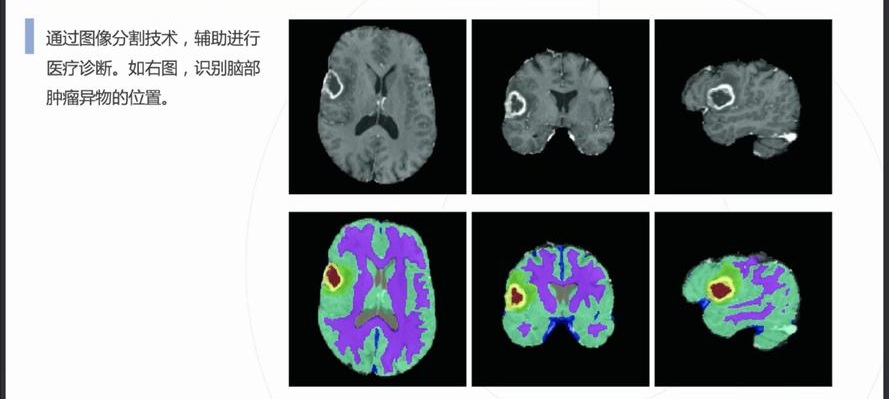

自動病灶檢測:借助計算機視覺和人工智能算法,CCD視覺檢測設(shè)備能夠自動識別醫(yī)學(xué)影像中的病灶區(qū)域,如腫瘤、炎癥、骨折等異常結(jié)構(gòu)。

早期癌癥篩查:在乳腺癌、肺癌、皮膚癌等癌癥的早期篩查中,CCD視覺檢測系統(tǒng)通過分析X光、MRI或CT掃描圖像,識別出腫瘤的早期跡象,顯著提高早期診斷率。